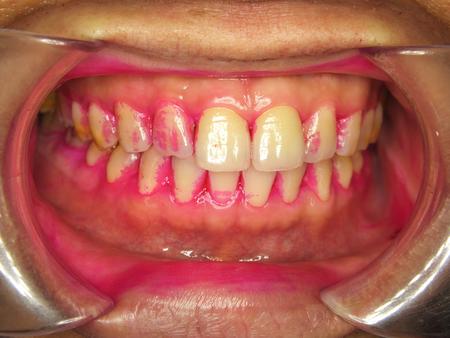

牙菌斑肉眼往往看不见,下面这张图上粉色的斑点就是菌斑指示剂染色后的牙菌斑。

很多朋友即使刷完牙齿后再进行染色,依然可以看见大量没有清除的牙菌斑,这便是由于刷牙方法不正确导致的。

图片来自网络

上图也可以看出牙菌斑堆积的位置:牙齿的缝隙以及牙龈的边缘。